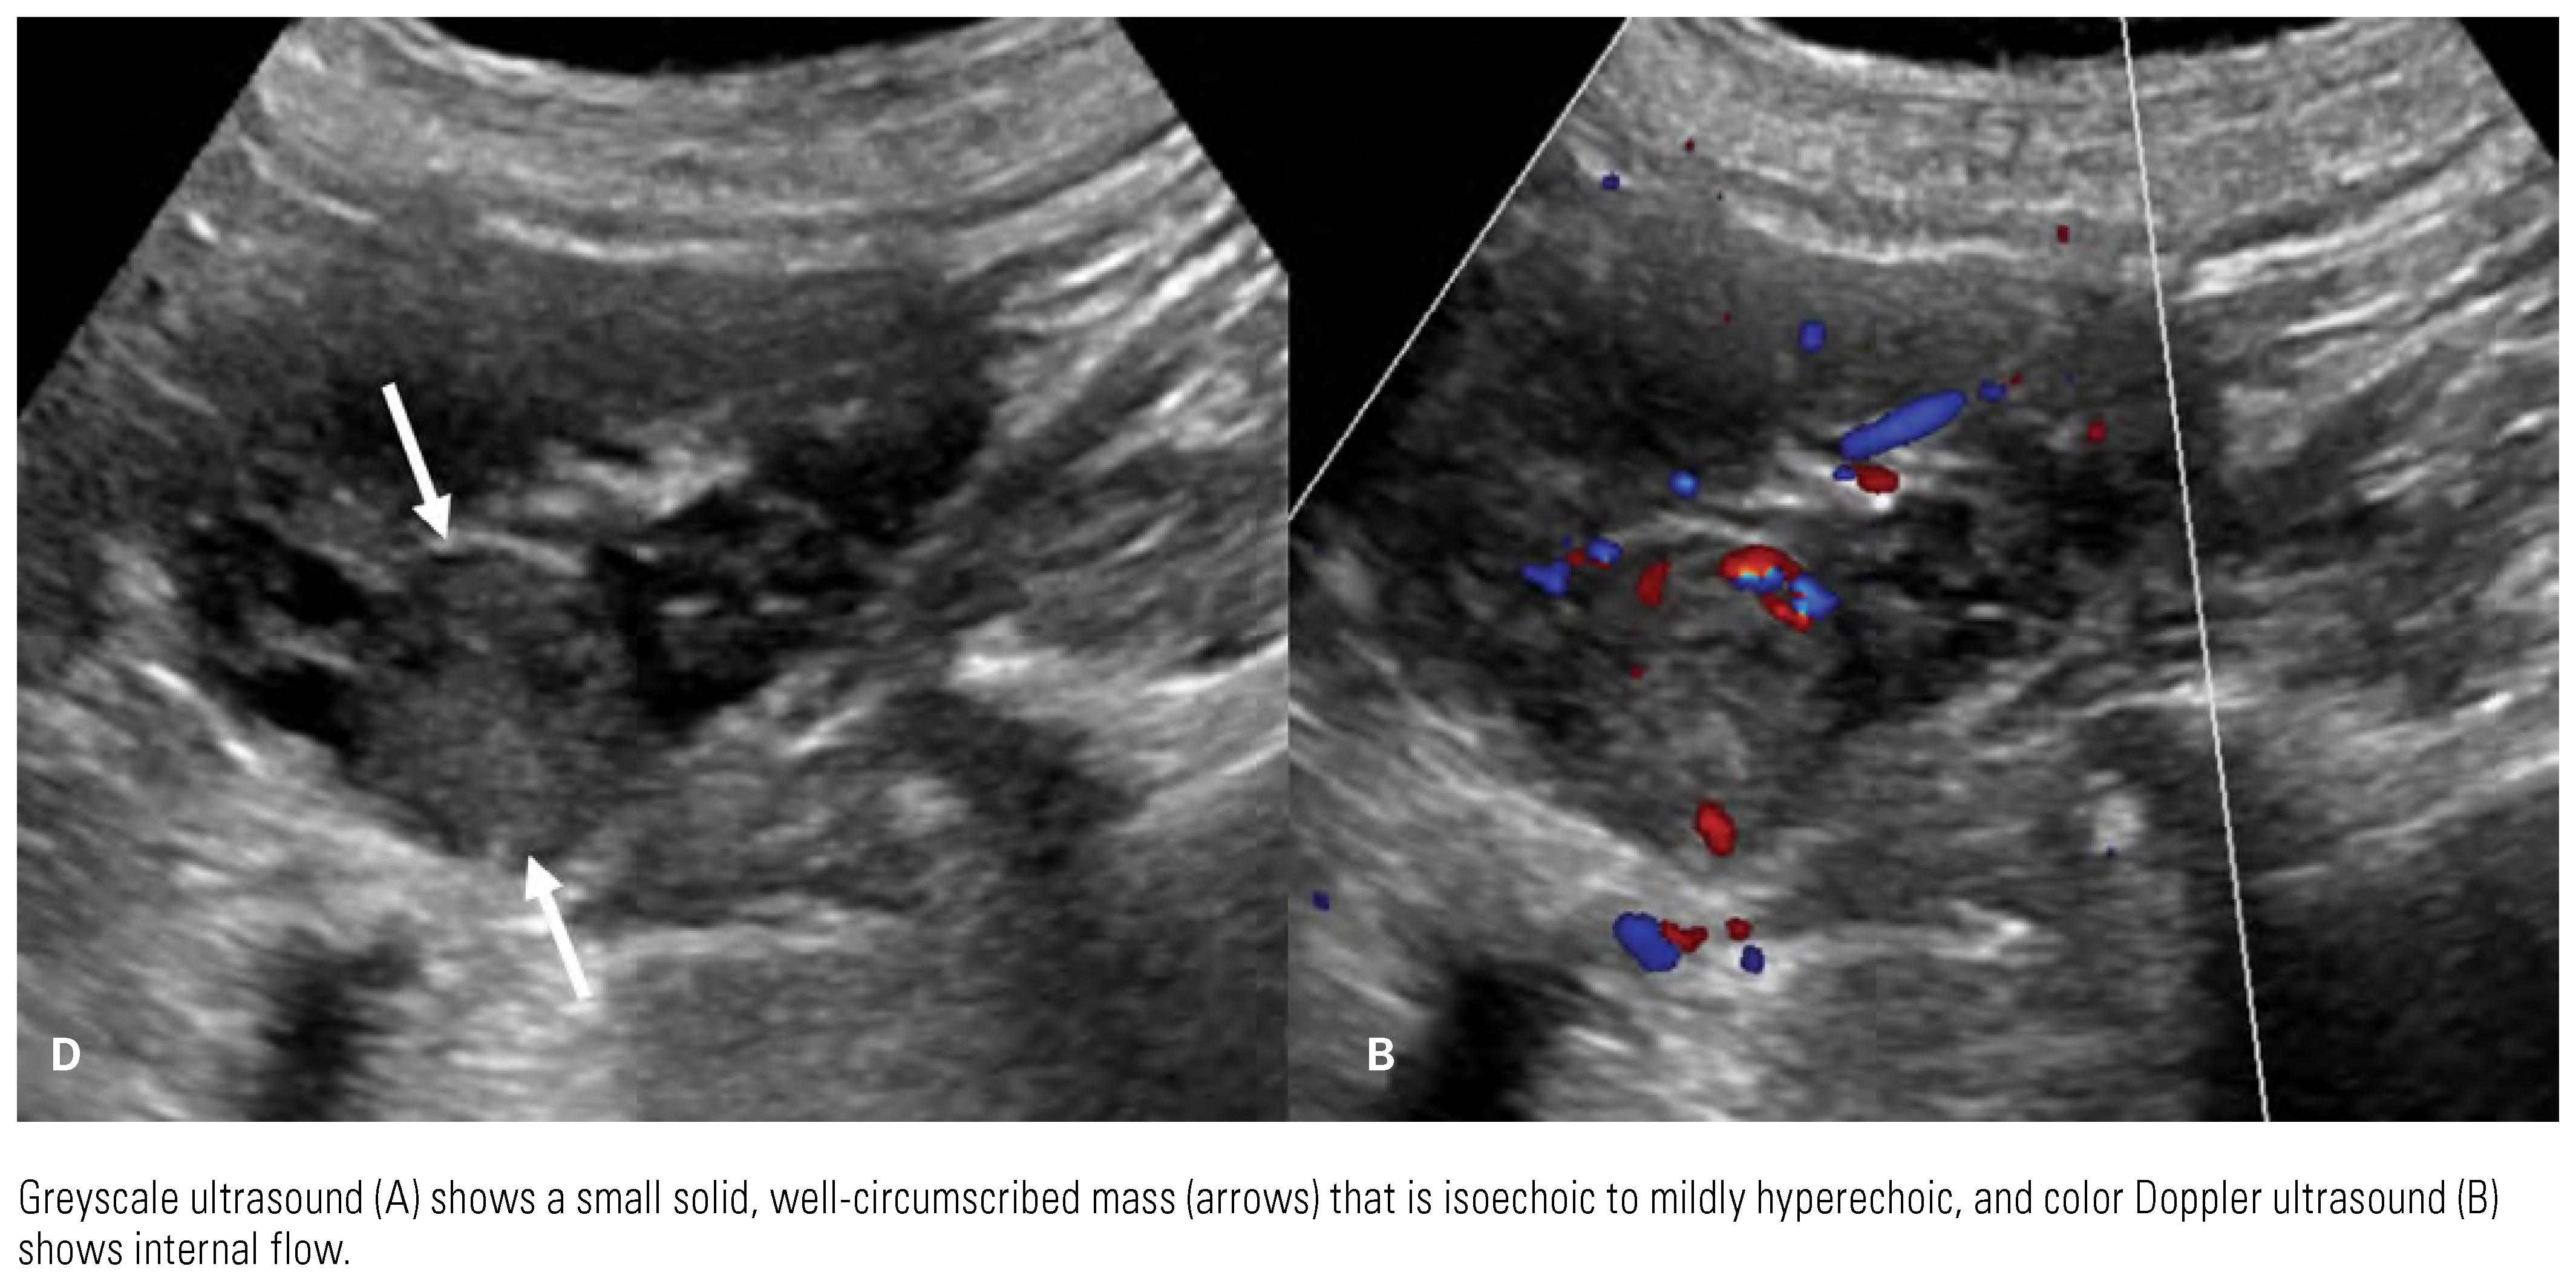

Detection and Diagnosis

Papillary Renal Cell Carcinoma